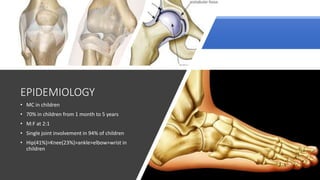

• MC in children

• 70% in children from 1 month to 5 years

• M:F at 2:1

• Single joint involvement in 94% of children

• Hip(41%)>Knee(23%)>ankle>elbow>wrist in

children

EPIDEMIOLOGY